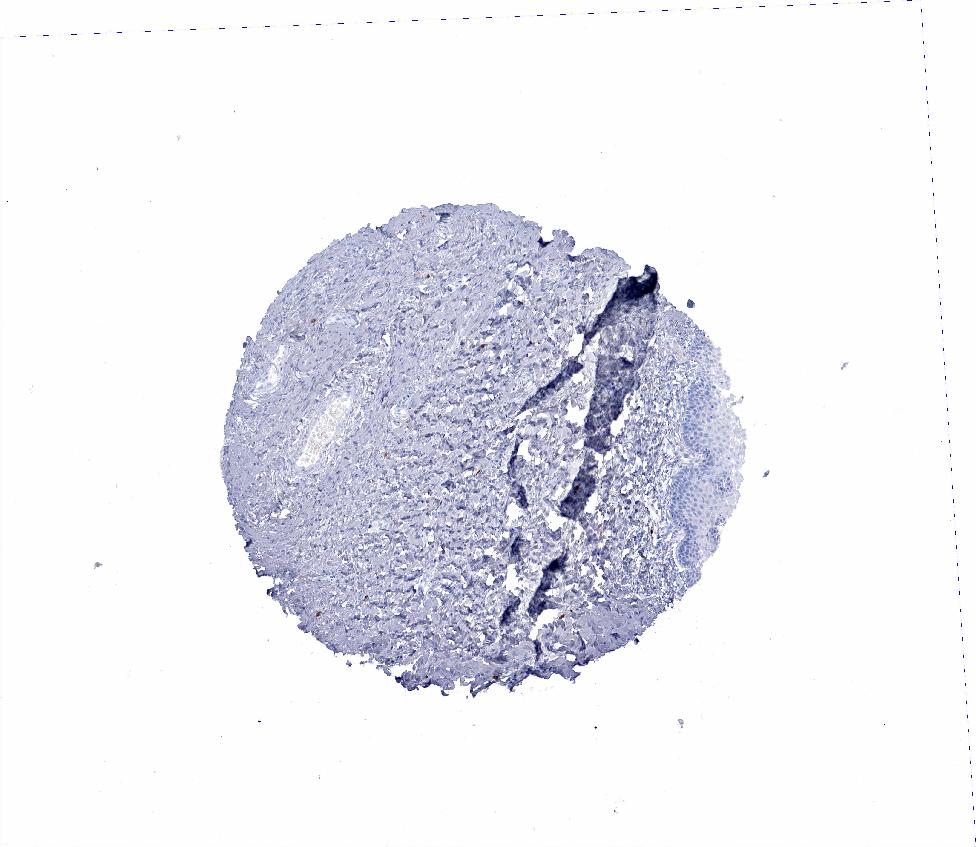

TISSUE PRIMARY DATA CERVIX Show tissue menu

CERVIX - Antibody stainingi

Antibody staining in the annotated cell types in the current human tissue is reported as not detected, low, medium, or high, based on conventional immunohistochemistry profiling in selected tissues. This score is based on the combination of the staining intensity and fraction of stained cells.

Each image is clickable and will lead to virtual microscopy that enables deeper exploration of all samples and also displays staining intensity scores, fraction scores and subcellular localization as well as patient and tissue information for each sample.

Antibody HPA056444Antibody CAB000019

Glandular cells Not detectedNot detected

Squamous epithelial cells Not detectedNot detected